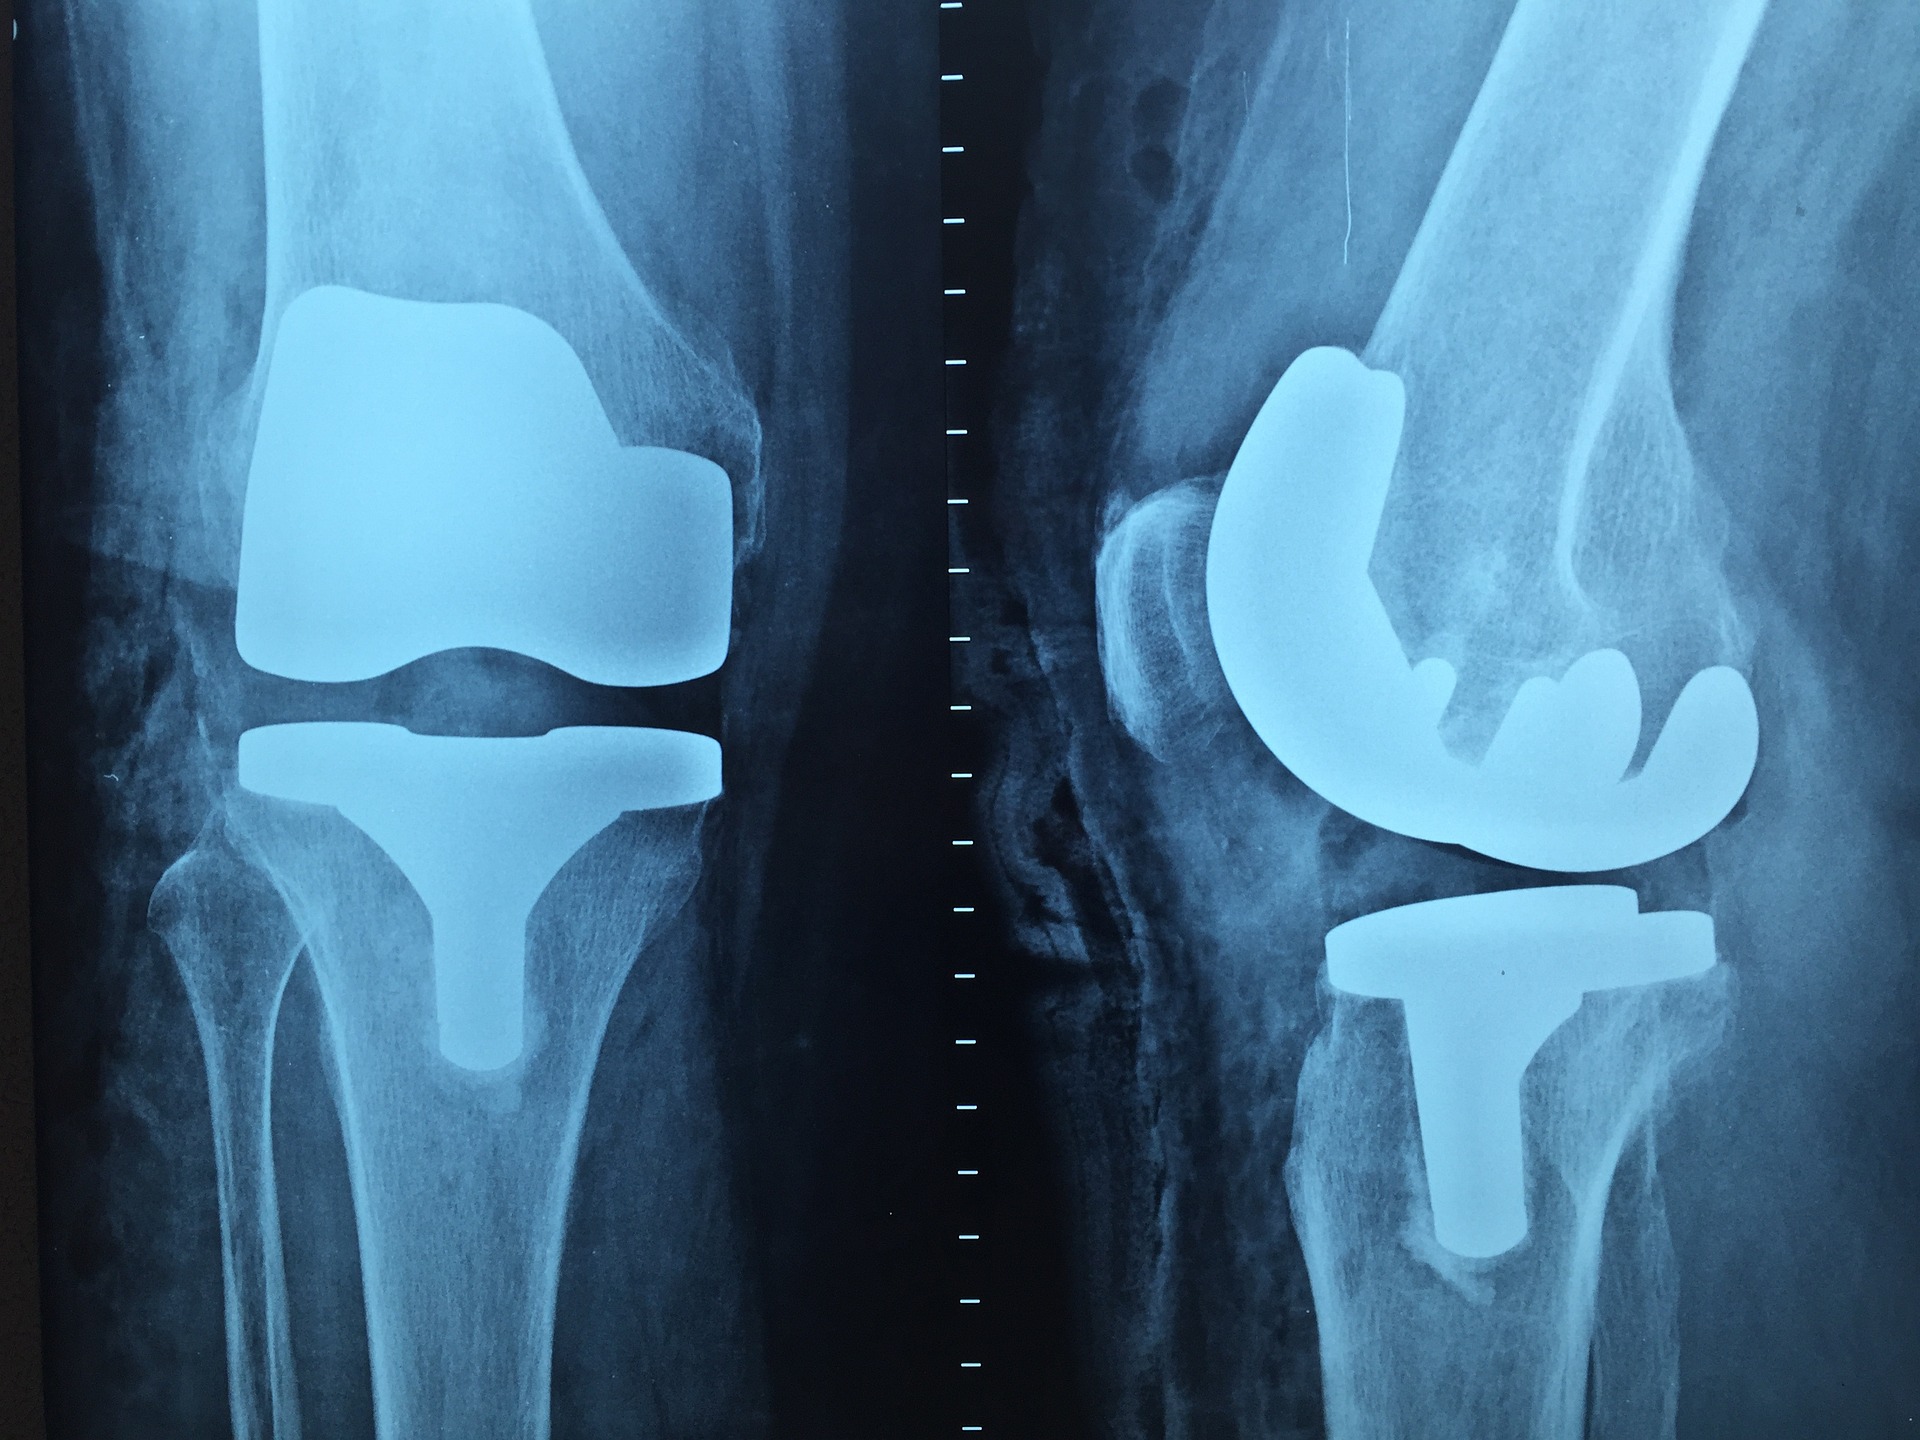

관절염 수술 치료 방법

관절염 수술 치료 방법으로는,

여러 가지가 있으나, 관절경을 이용하여 뼈 모양을 올바르게

만들어서 관절에 충격을 조금 줄이는 절골술을 시행하거나,

관절 연골 이식과 혹은 인공 관절을 넣는 방법 등으로 수술 치료 방법을

볼 수 있습니다.

다만, 관절염 수술 치료 방법에서는

가장 최후의 치료 방법이다라는 것을 꼭 명심하시는 것이 좋습니다.